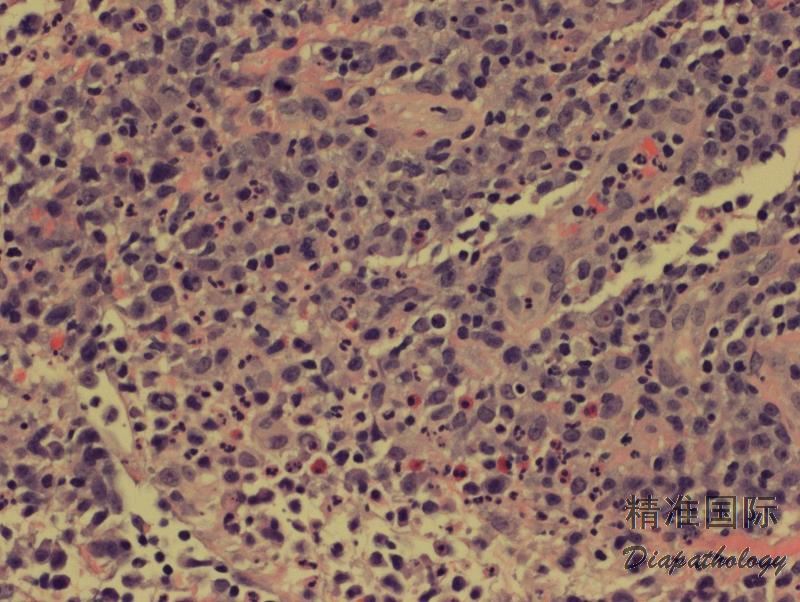

低倍镜下,真皮病变区域多为楔形,但组织形态变异很大,部分是由于反映了病变的不同阶段。目前分为至少 6 种亚型。A 型:最常见(>80%)。散在的 CD30+异形单核、多核或 HRS 样大细胞混合于大量炎性背景细胞(小淋巴细胞、组织细胞、中性和嗜酸性粒细胞)。B 型:少见(<5%)。中小异型淋巴细胞(CD30+/-),含不规则和或脑回样核,呈现亲表皮侵润,与 MF 类似。C 型(约 10%):大异形细胞成片状侵润(CD30+),背景可有少量炎性细胞,此型与 C-ALCL 类似。 D 型(<5%):中小异形淋巴细胞强亲表皮性侵润,表达 CD8 和 CD30,类似原发性皮肤 CD8+侵袭性亲表皮细胞毒 T 细胞淋巴瘤。E 型(<5%):中小异形、多形性细胞(CD8+、CD30+)呈现血管中心性、血管破坏性浸润伴出血、坏死,临床表现为斑块结节病变,并很快形成溃疡,进而变成大的坏死结痂病灶。LyP 伴 6p25.3 重排(<5%):此型特征是有 DUSP22-IRF4 易位,组织学见中小异形脑回样核细胞(CD30 弱+)亲表皮浸润,伴中到大细胞(CD30 强+)真皮层浸润,类似 MF 大细胞转化。此外,还有其它罕见类型,如亲毛囊型、肉芽肿样型等。同一病例可以同时存在不同的组织学亚型。认识这些不同的亚型可以避免过度诊断为 T 细胞肿瘤。